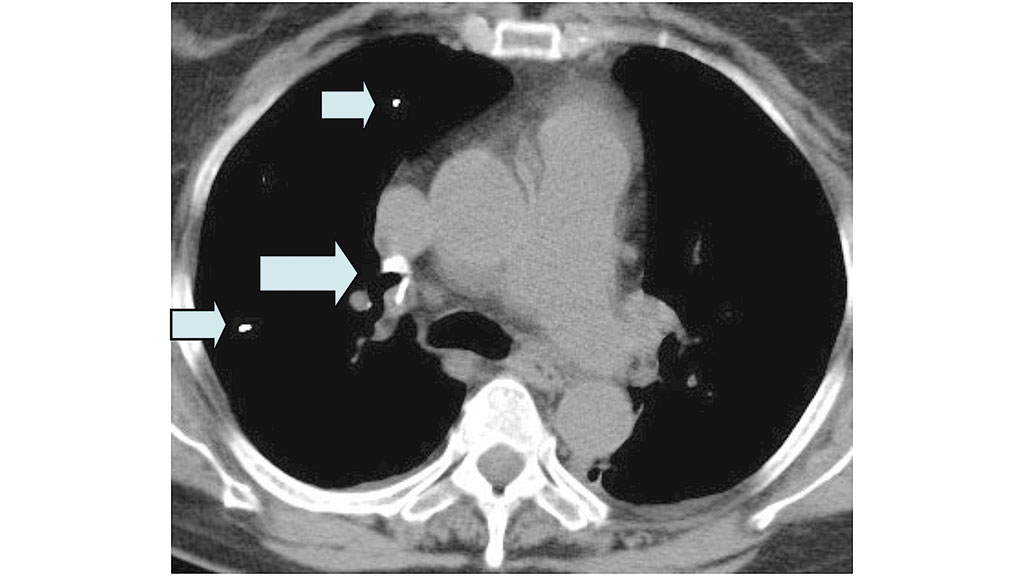

Obwohl die Komplikationsmöglichkeiten im Rahmen des Eingriffes neben den allgemeinen Operationsrisiken der Wirbelsäulenchirurgie (Blutung, Verletzung der Dura und gegebenenfalls des Myelons etc.) teilweise vital bedrohliche Ereignisse wie z. B. ausgeprägte Zementembolien (Abb. 4 bis 6) umfassen, fehlt den Verantwortlichen teilweise die erforderliche Kompetenz, diese Komplikationen zu beherrschen 23 24 25. Trotz der geringen Operationsdauer von durchschnittlich 20 bis 30 Minuten pro Wirbelkörper bedeutet alleine schon die für die Operation erforderliche Bauchlagerung für alte und multimorbide Patienten eine zusätzliche Belastung – in seltenen Fällen kommt es intraoperativ zu Kreislaufstillständen mit Todesfolge, auch wenn Reanimationsmaßnahmen sofort greifen und eine Weiterbehandlung auf einer Intensivstation (kleinere Krankenhäuser verfügen teilweise über keine ITS) gewährleistet ist.